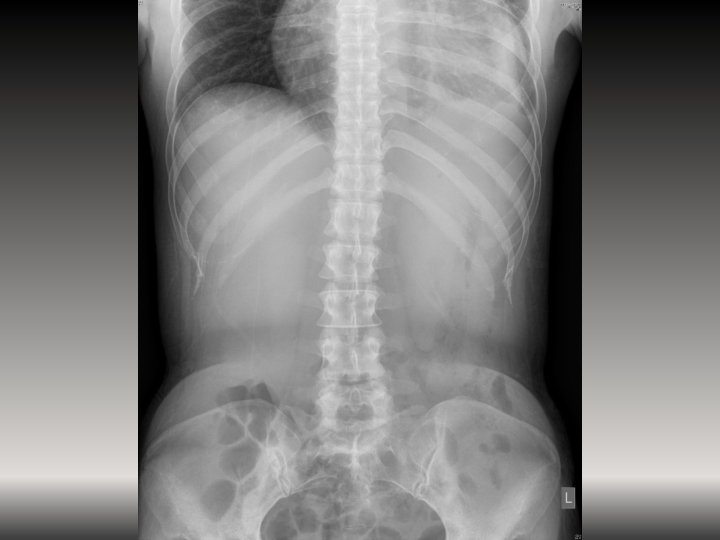

Case 2 • A 70 -year-old man presented with back pain for 6 months.

Case 2 • A 70 -year-old man presented with back pain for 6 months. This is the x-ray:

Case 2 1. What are the x-ray findings? (4 marks) 2. What is the

Case 2 1. What are the x-ray findings? (4 marks) 2. What is the provisional diagnosis? (1 mark) 3. What are the common causes for the diagnosis? (3 marks out of 5) 4. What other symptoms may this patient present? (2 marks out of 3) 5. What are the complications that this patient may suffer from? (2 marks)